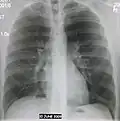

AP CXR showing right lower lobe pneumonia -

AP CXR showing pneumonia of the lingula of the left lung -